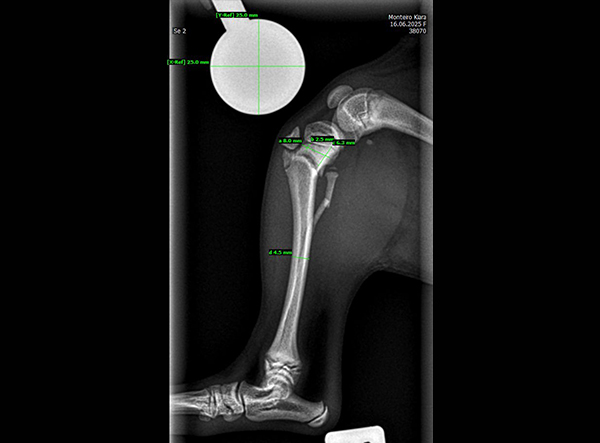

The patient, an 18-week-old female Yorkshire Terrier, was referred for surgery on October 21, 2025. The dog had sustained a fall from the owner’s arms, resulting in a fracture of the proximal tibial metaphysis just below the growth plate, along with a fibular fracture. Given the patient’s very small size and young age, precise anatomical fixation and minimal disruption of the growth zone were essential.

An open reduction and internal fixation (ORIF) was performed via a medial approach to the proximal tibia.Implant Used: 1.5 mm LeiLOX TPLO Swing Titanium Plate

- Micro-Precision Fit: Perfectly adapted to miniature canine bone anatomy.

- Stable Fixation: Maintains optimal alignment during bone healing.

- Growth-Friendly Design: Allows secure fixation without compromising nearby physes.

The surgery was completed without complications. Postoperative radiographs confirmed anatomical alignment and stable fixation. With careful rehabilitation, the young Yorkshire Terrier is expected to regain full function and resume normal activity pain-free.